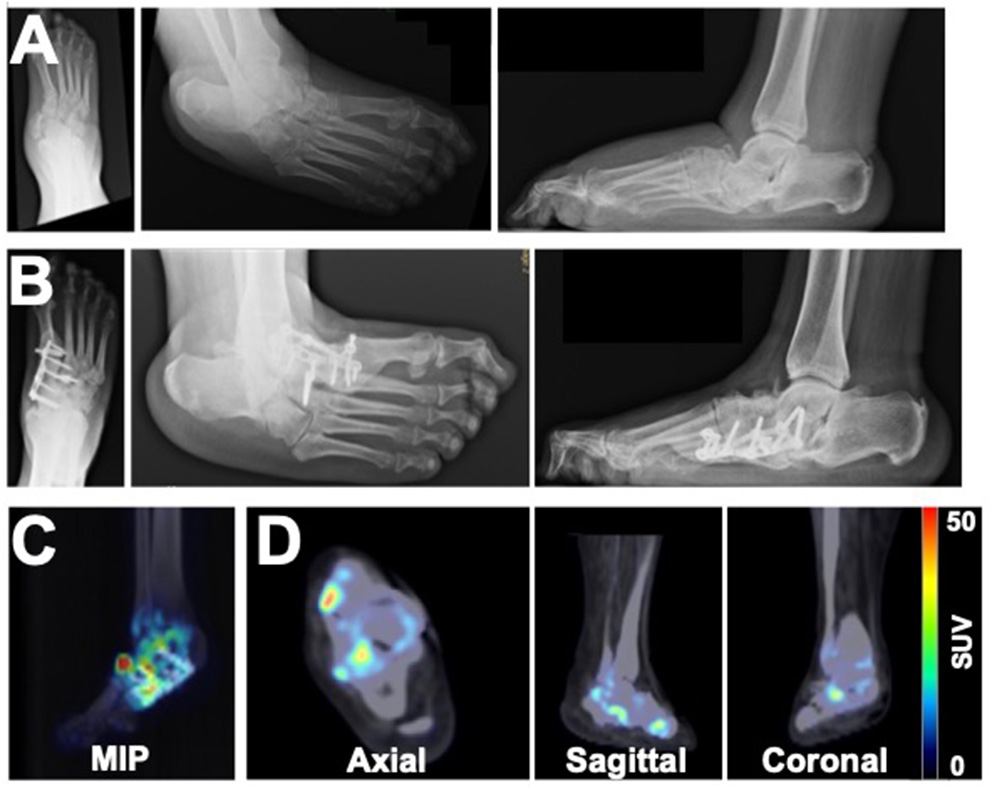

Patient 1 initially presented with a chronic left foot wound deep to the level of bone. MRI was consistent with osteomyelitis of the navicular bone as well as the medial and middle cuneiform bones. The patient also had a history of CN due to type 2 DM. Conservative treatment options were exhausted, and the patient underwent surgical intervention. External fixation was applied to the medial foot, which consisted of a Biomet Mini-Rail and four half pins across the mid-tarsal joint (Figure 1A) that were then removed 2 months later. Five years after surgery, radiography demonstrated stable bone structures (Figure 1B). PET/CT images were also acquired 5 years after surgery and revealed focal uptake of 18F-NaF within the bones of the foot with CN, which suggested ongoing bone remodeling 5 years post-surgical reconstruction (Figures 1C,D).

Figure 1

Multimodality imaging evaluation of a 65-year old male patient with a history of Charcot foot, type 2 DM, and PAD. X-rays acquired at (A) the time of external fixation and (B) 5 years after surgery reveal the architecture of the foot. (C) Maximum intensity projection (MIP) images and (D) axial, sagittal, and coronal 18F-NaF PET/CT images of the foot 5 years after surgery demonstrate focal increased uptake of 18F-NaF in the bones of the foot, indicating ongoing physiological remodeling of the afflicted foot 5 years after surgical reconstruction.